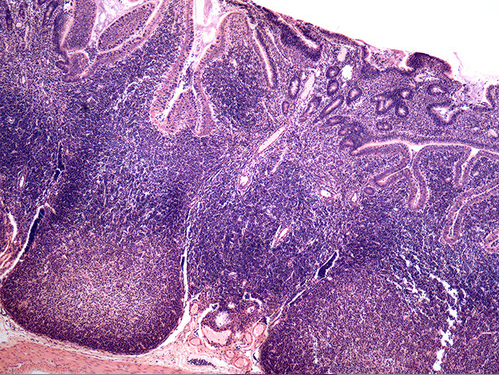

pharyngeal tonsil

The structure marked by the green arrow is a palatine tonsil

This photomicrograph illustrates diffuse lymphatic tissue found just deep to the stratified squamous epthelium in the walls of the pharynx.

The green arrow is indicating a tonsilar crypt